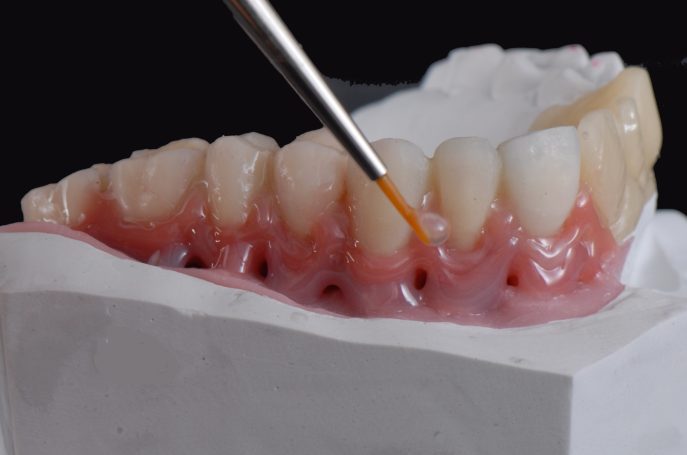

Teleskopierende Brücken im digitalen Ablauf hergestellt.

Implantatbrücke zur Wiederherstellung der Zahn- und Zahnfleischanteile mit verschraubten Brücken.